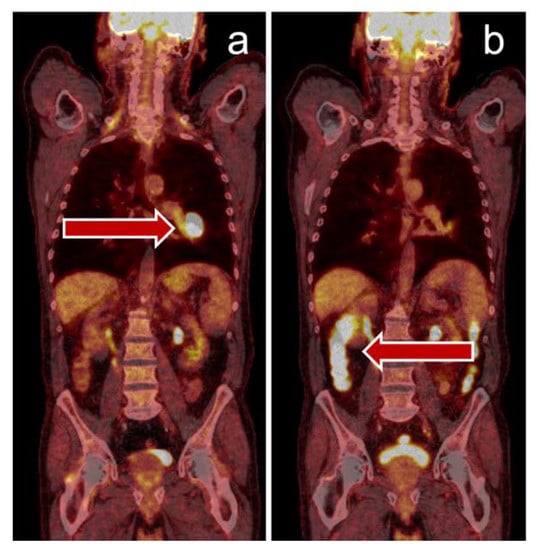

- Winer, A.; Ghatalia, P.; Bubes, N.; Anari, F.; Varshavsky, A.; Kasireddy, V.; Liu, Y.; El-Deiry, W.S. Dual Checkpoint Inhibition with Ipilimumab plus Nivolumab After Progression on Sequential PD-1/PDL-1 Inhibitors Pembrolizumab and Atezolizumab in a Patient with Lynch Syndrome, Metastatic Colon, and Localized Urothelial Cancer. Oncologist 2019, 24, 1416–1419. [Google Scholar] [CrossRef] [PubMed]

- Iravani, A.; Osman, M.M.; Weppler, A.M.; Wallace, R.; Galligan, A.; Lasocki, A.; Hunter, M.O.; Akhurst, T.; Hofman, M.S.; Lau, P.K.H.; et al. FDG PET/CT for tumoral and systemic immune response monitoring of advanced melanoma during first-line combination ipilimumab and nivolumab treatment. Eur. J. Nucl. Med. Mol. Imaging 2020, 47, 2776–2786. [Google Scholar] [CrossRef] [PubMed]

- Mekki, A.; Dercle, L.; Lichtenstein, P.; Marabelle, A.; Michot, J.-M.; Lambotte, O.; Le Pavec, J.; De Martin, E.; Balleyguier, C.; Champiat, S.; et al. Detection of immune-related adverse events by medical imaging in patients treated with anti-programmed cell death 1. Eur. J. Cancer 2018, 96, 91–104. [Google Scholar] [CrossRef]